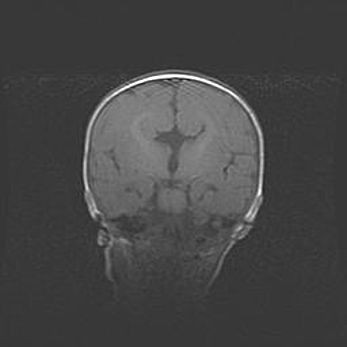

Церебральная ишемия II.

Возраст: 5 дней

Вес: 3400 г

Пол: женский

Окружность головы: 35 см

Срок гестации: 39 недель

Церебральная ишемия – это заболевание, характеризующееся недостаточностью (гипоксией) либо полным прекращением (аноксией) снабжения мозга кислородом по причине закупорки одного или нескольких сосудов. Это приводит к  что метаболическим расстройствам различной степени тяжести в тканях головного мозга, развитию коагуляционных некрозов и гибели нейронов.